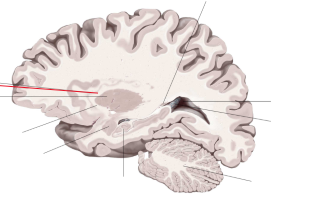

corpus callosum

lobus frontalis

lobus parietalis

lobus occipitalis

lobus temporalis

insula

gyrus cinguli

sulcus centralis

sulcus cinguli

fornix